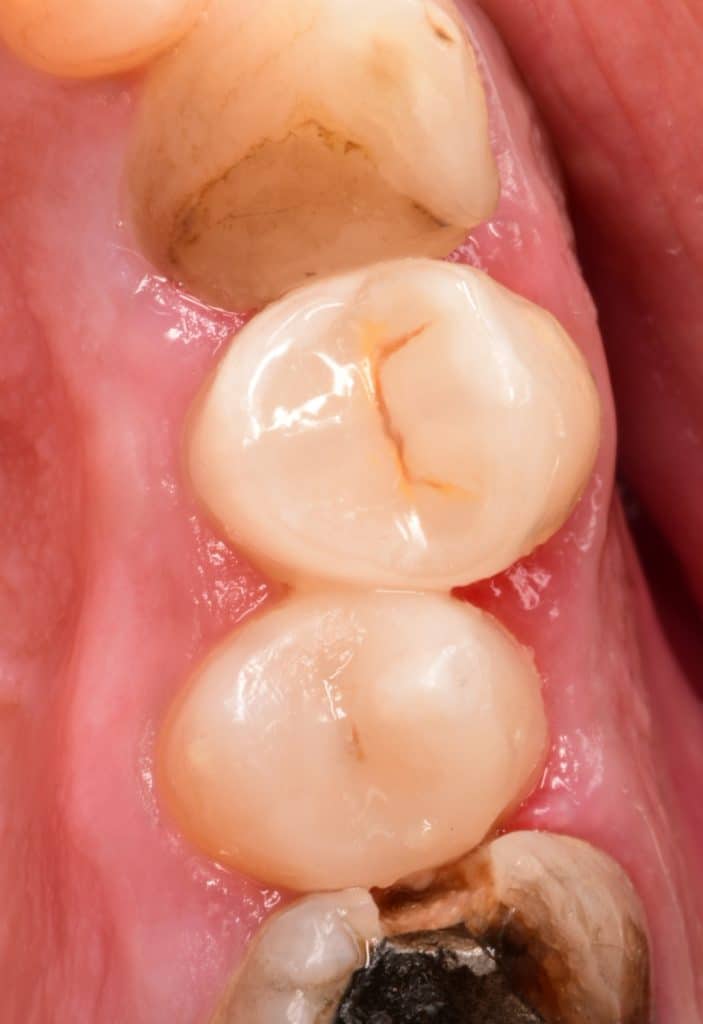

Second premolar done firstly and then the biobase of the first premolar created and adjusted to the adjacent teeth

You can see the buccal extension of the preparation for more esthetic, this is the veneerlay preparation